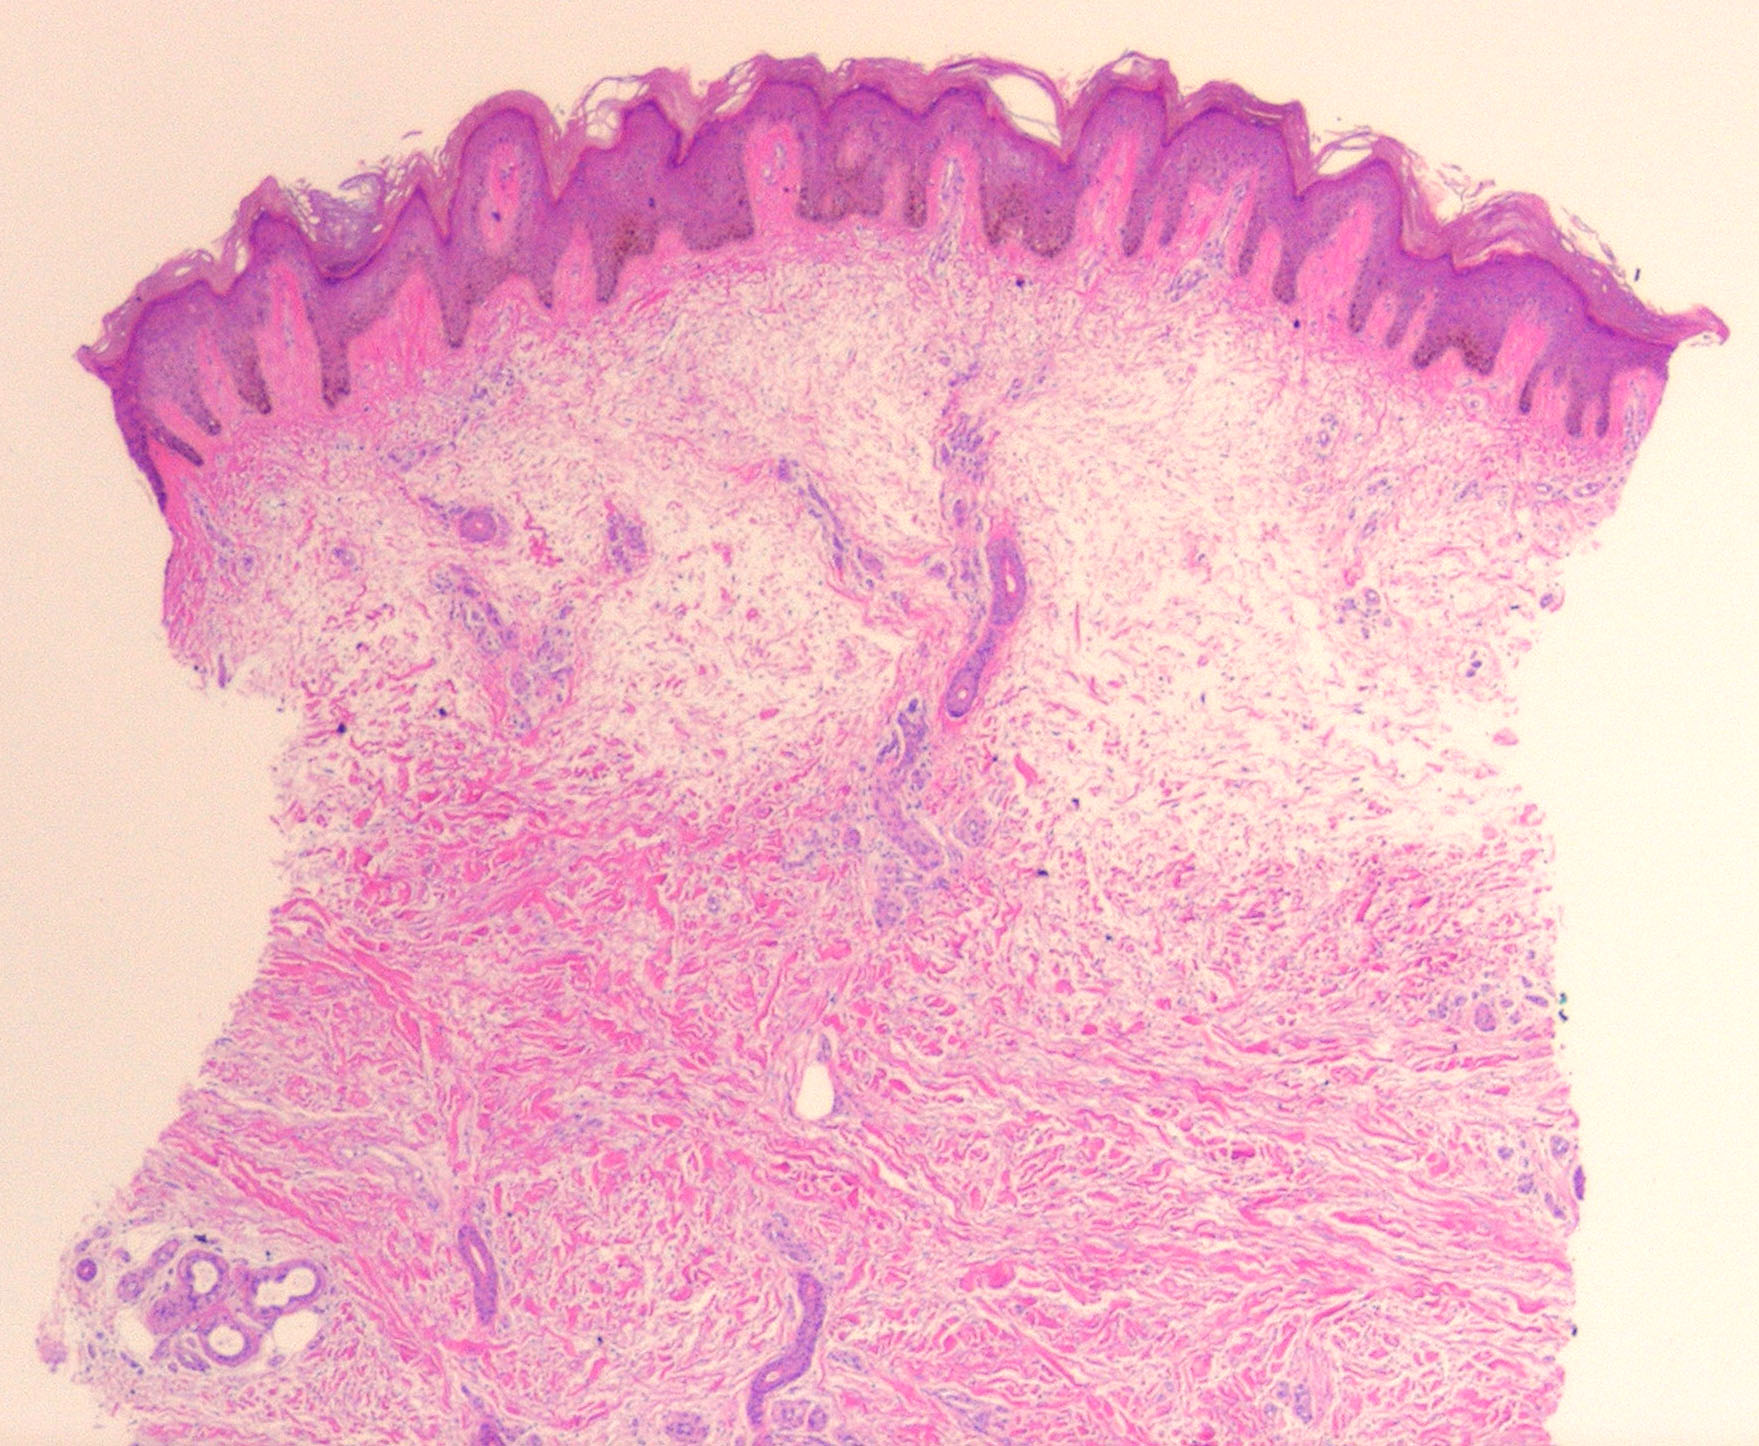

The epidermis and papillary dermis are usually normal. Mucin in large amounts is present in the dermis,

particularly in the upper half . As a result, the dermis is greatly thickened. The mucin occurs not only as individual threads and granules but also as extensive deposits resulting in the splitting up of collagen bundles into fibers and wide separation of the fibers. As a result of shrinkage of the mucin during the process of fixation and dehydration, there are empty spaces within the mucin deposits. The number of fibroblasts is not increased as a rule, but in areas where there is much mucin, some fibroblasts have a stellate shape and are then referred to as mucoblasts . A perivascular infiltrate of lymphocytes may be seen in some cases, and mast cells are moderately increased in number .